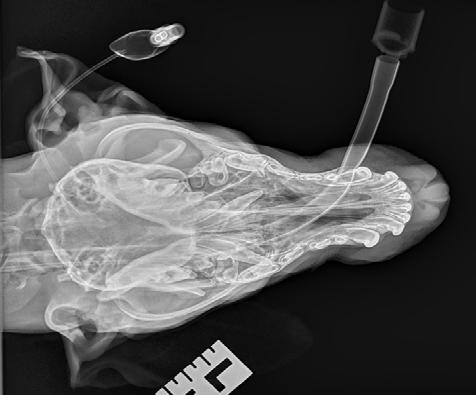

Radiographs (Figure 2) were performed of the nose and possibly some atrophy of the nasal turbinates could be appreciated; however, it was not extensive. Richard Malik noted for ‘next time’ the best radiographic view to perform is an open mouth with the X-ray plate placed into the mouth as far as it will go. Alternatively, CT would offer superior imaging and could be considered if wanting to explore the extent of the destruction, for example to determine if the cribriform plate was breached or the sphenoid sinus was infected, although it was not an option in this case due to cost considerations.